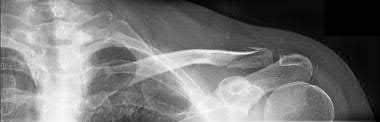

2. # A 35-year-old woman is involved in a head-on collision while driving. Initial radiographs are shown in Figures 8a and 8b. Injury to what vessel increases the risk for osteonecrosis of the injured bone?

1. Dorsalis pedis artery

2. Perforating peroneal artery

3. Lateral tarsal artery

4. Artery of the tarsal canal

5. Artery of the tarsal sinus Corrent answer: 4

The patient has a Hawkins type III talar neck fracture-dislocation with a risk of osteonecrosis ranging from 69% to 100%. Anatomic studies have shown that the artery of the tarsal canal supplies the lateral two thirds of the talar body.

The other vessels listed provide no significant contribution to the talus.